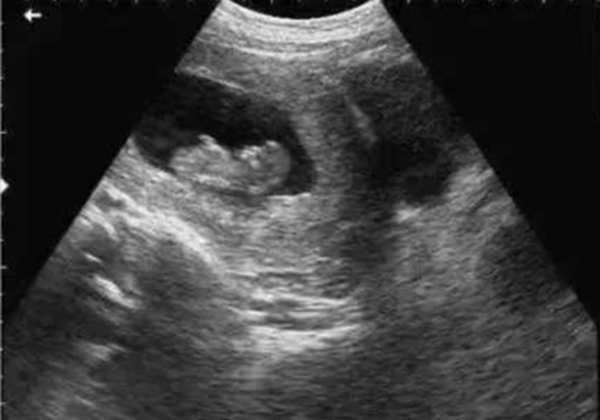

? 超聲檢查(B超/彩超):它利用超聲波的反射原理成像,就像“用聲音給身體拍照片”,沒有任何輻射。無論是孕期產(chǎn)檢(觀察胎兒發(fā)育)、腹部檢查(排查肝脾膽囊問題),還是甲狀腺、乳腺等淺表器官檢查,超聲都是首選。而且超聲檢查靈活便捷,還能實(shí)時(shí)動態(tài)觀察器官運(yùn)動(比如心臟跳動、胎兒胎動),是臨床中應(yīng)用最廣泛的“安全檢查”。